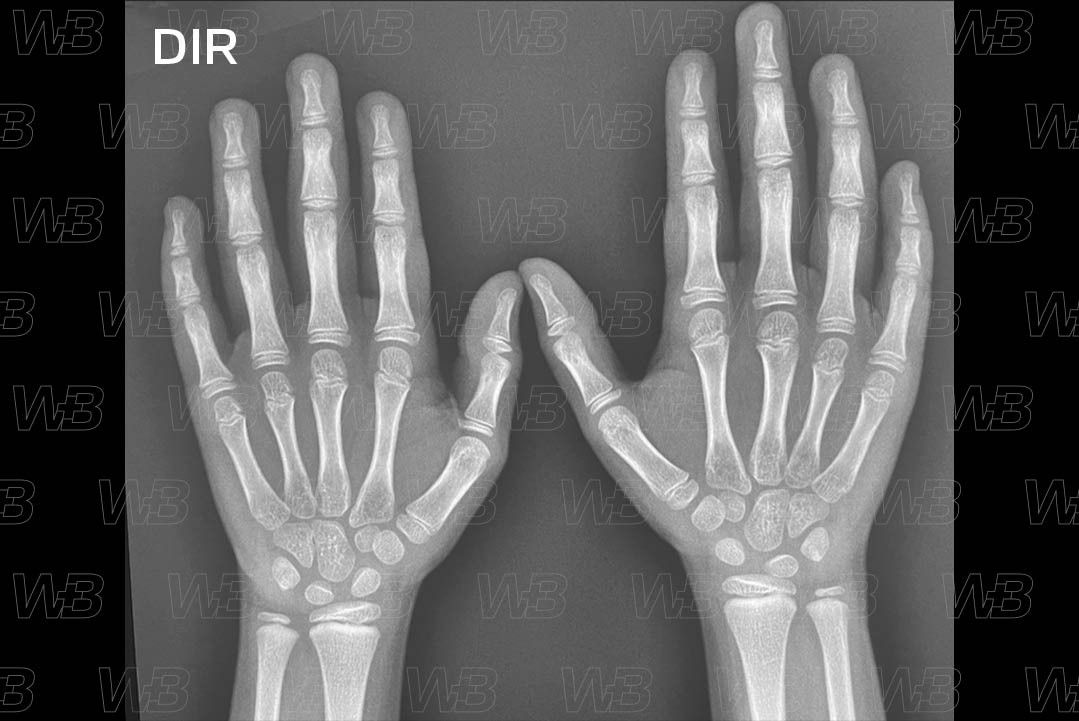

Atlas idade óssea - Feminino - 6 anos e 10 meses

RADIOGRAFIA MÃOS E PUNHOS (IDADE ÓSSEA)

Feminino

6 anos e 10 meses:

• Epífise ulnar.